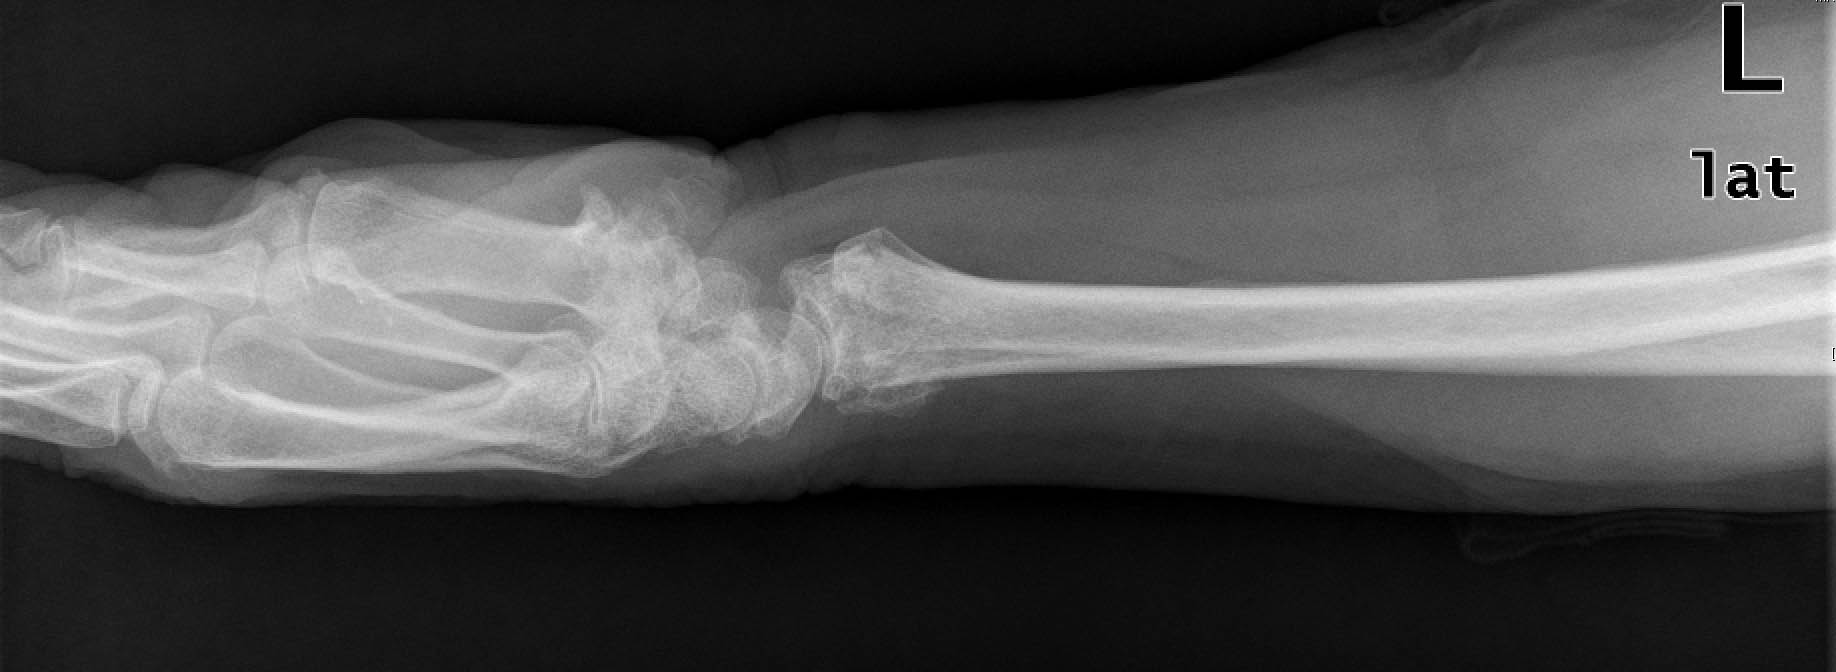

ACT Alteraciones degenerativas en muñeca.